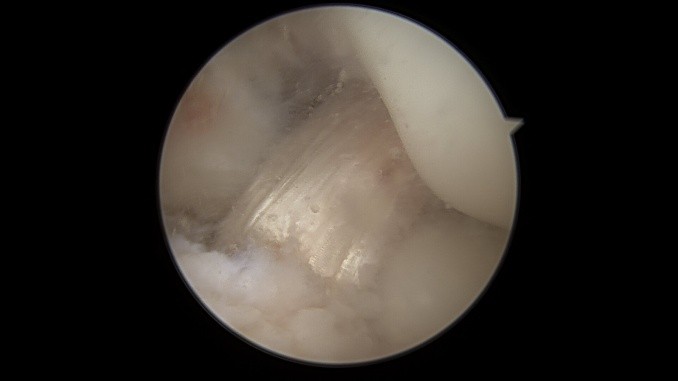

Als Behandlungsmöglichkeiten für Knorpelschäden gibt es die sog. Abrasionschondroplastik / Mikrofrakturierung, bei der der defekte Knorpel bis auf den Knochen abgetragen und dieser dann mit kleinen Löchern perforiert und ggf. mit einer speziellen Membran bedeckt wird. Durch die Perforationen tritt Knochenmark in den Defekt ein und es bildet sich ein sog. Regeneratknorpel. Auch die Möglichkeit einer Knorpelzelltransplantation (sog. „ACT“) wird bei uns angeboten. Hier werden in einer ersten Operation Knorpelzellen entnommen und in einer zweiten Operation in den Defekt eingebracht (entweder als sog. ACT Inject in einer Suspension oder als ACT 3d auf einer Membran). Auch die körpereigene Transplantation eines Knochen-Knorpel-Zylinders (OATS / Mosaikplastik) ist eine Therapiemöglichkeit, die wir anbieten können.